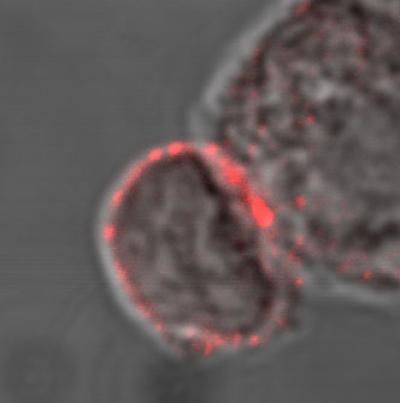

For T cells to detect and kill foreign pathogens such as clumps of bacteria or viruses, the cells must first be 'triggered' into action and 'transform' from inactive and harmless immune cells into killer cells that are primed to seek out and destroy all traces of a foreign pathogen.

In order for the specialized immune cells (T cells) to protect the body from dangerous viruses or bacteria, the T cells must first be exposed to traces of the foreign pathogen. This occurs when they are presented by other immune cells in the body (known as macrophages) with suspicious 'cell fragments' or 'traces' of the pathogen. The T cells then bind to the fragment and divide and multiply into hundreds of identical cells that are all focused on the same pathogen type. The sequence of chemical changes that the T cells undergo enables them to both be 'sensitized to' and able to deliver a targeted immune response.

Professor Carsten Geisler from the Department of International Health, Immunology and Microbiology explains that "when a T cell is exposed to a foreign pathogen, it extends a signaling device or 'antenna' known as a vitamin D receptor, with which it searches for vitamin D. This means that the T cell must have vitamin D or activation of the cell will cease. If the T cells cannot find enough vitamin D in the blood, they won't even begin to mobilize. "

T cells that are successfully activated transform into one of two types of immune cell. They either become killer cells that will attack and destroy all cells carrying traces of a foreign pathogen or they become helper cells that assist the immune system in acquiring "memory". The helper cells send messages to the immune system, passing on knowledge about the pathogen so that the immune system can recognize and remember it at their next encounter. T cells form part of the adaptive immune system, which means that they function by teaching the immune system to recognize and adapt to constantly changing threats.

The research team was also able to track the biochemical sequence of the transformation of an inactive T cell to an active cell, and thus would be able to intervene at several points to modulate the immune response. Inactive or 'naïve' T cells crucially contain neither the vitamin D receptor nor a specific molecule (PLC-gamma1) that would enable the cell to deliver an antigen specific response.